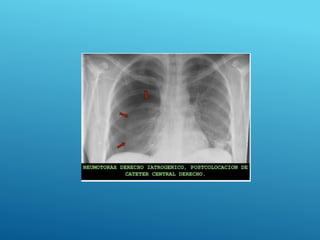

HEMOTÓRAX DERECHO

HEMONEUMOtórax

24/03/2017